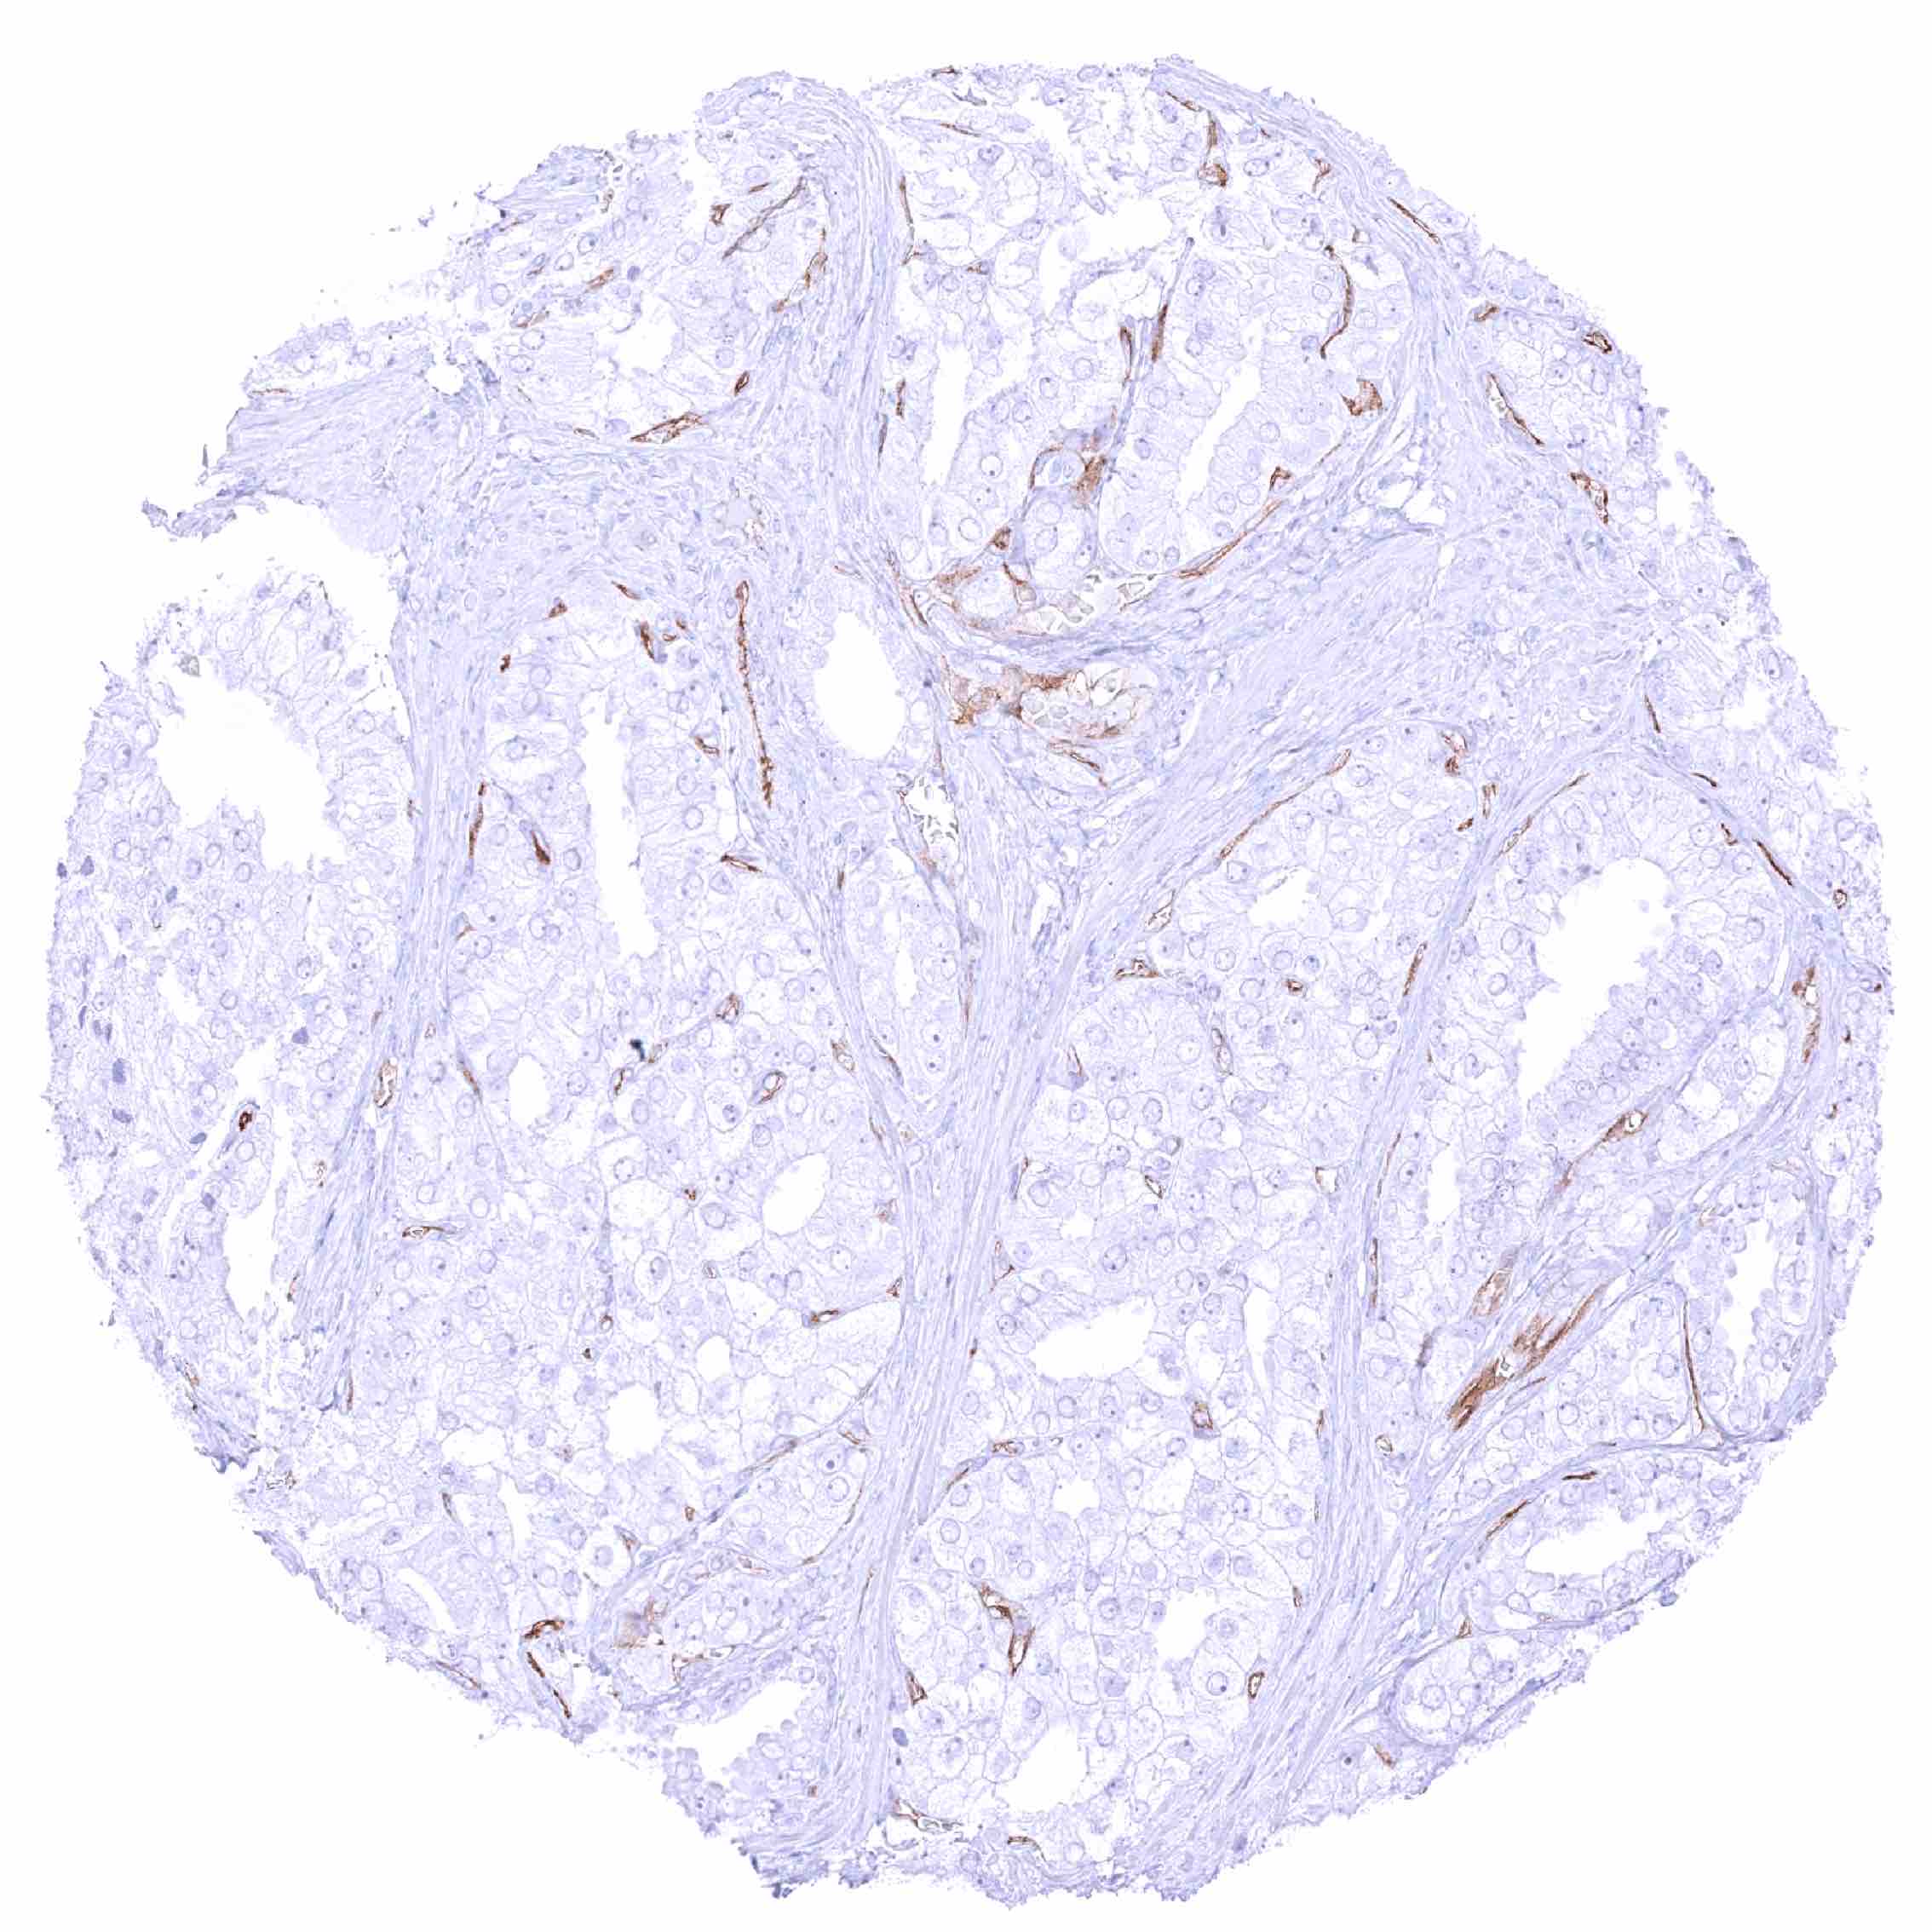

Colon – PODXL negative colorectal adenocarcinoma. Distinct PODXL positivity of endothelial cells of tumor associated vasculature.